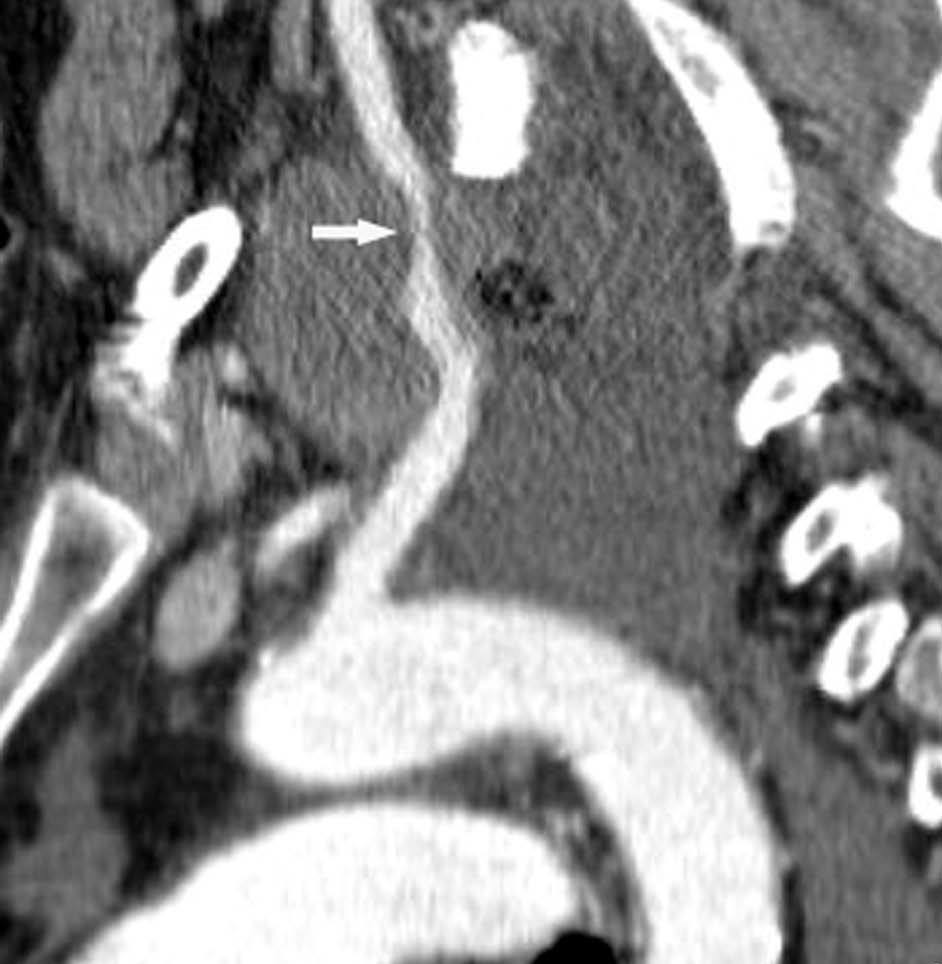

Valoración del tumor

El estadio tumoral (T) se basa en el tamaño, localización y relación con las estructuras adyacentes valorado mediante TC. Los tumores T1 son aquellos de 3 cm o menores en su diámetro mayor, rodeados de pulmón y que no invaden la pleura visceral ni los bronquios principales, mientras que los T2 son lesiones mayores de 3 cm, o aquellas que invaden la pleura visceral o al bronquio principal a más de 2 cm de la carina o que condicionan atelectasia o neumonitis obstructiva que no afecte a todo el pulmón. La diferenciación entre ambos estadios tumorales suele ser sencilla mediante TC, salvo la afectación de la pleura visceral, aunque esta no tiene un impacto importante en el manejo clínico. El tumor T3 viene determinado por la infiltración de estructuras vecinas potencialmente resecables, como la pared torácica, diafragma, pleura mediastínica, pericardio parietal o si el tumor está situado a menos de 2 cm de la carina (fig. 1). Los tumores T4 son aquellos que no pueden ser resecados porque engloban a estructuras vitales, invaden el corazón, grandes vasos, esófago o cuerpos vertebrales (fig. 2) o en los que existe un nódulo o nódulos en el mismo lóbulo del tumor. Además de definir la T, es importante reflejar las particularidades de la infiltración de estructuras en vecindad que puedan modificar la actitud terapéutica. Por ejemplo, cambiará la estrategia quirúrgica según el tipo de bronquio afecto o la estructura mediastínica infiltrada, si es sólo la grasa, o un vaso; cuando existe neumonitis o atelectasia secundaria a un tumor central, la planificación del campo de radioterapia dependerá del límite entre la masa y la repercusión pulmonar.

Fig. 1.--T3. (A) Reconstrucción multiplanar (MPR) de tomografía computarizada (TC) torácica con contraste con ventana de pulmón. Atelectasia completa del lóbulo inferior derecho secundario a tumor endobronquial situado a menos de 2 cm de la carina (flecha hueca). (B) La misma reconstrucción con ventana de mediastino muestra el tumor (flechas) diferenciado de la atelectasia (asterisco). Derrame pleural (DP).

La diferenciación entre tumores T3 y T4 puede ser difícil empleando sólo técnicas de imagen. Cuando se evidencia destrucción ósea (costal o vertebral), existe masa en el espacio intercostal (fig. 3), o las estructuras mediastínicas están claramente englobadas por el tumor, el diagnóstico es obvio (fig. 2). Sin embargo, sin estos hallazgos, la predicción de invasión es mucho menos fiable. Se han descrito diferentes signos que pueden ayudar a determinar la invasión de pared torácica. Éstos incluyen el contacto con la superficie pleural mayor de 3 cm, el engrosamiento pleural, la ausencia de plano graso y la presencia de un ángulo obtuso entre el tumor y la pared torácica. Aplicando al menos dos de estos criterios la sensibilidad es de un 87%, sin embargo la especificidad es baja (59%)4. El dolor torácico localizado es un síntoma importante que a menudo está asociado a invasión de pared.

Fig. 2.--T4. (A) Corte axial de tomografía computarizada (TC) torácica con contraste. Tumor hiliar derecho que infiltra la arteria pulmonar derecha, la vena cava superior y engloba al bronquio intermediario. (B) Reconstrucción coronal oblicua, longitudinal al eje de la arteria pulmonar derecha, que muestra cómo engloba el tumor a la rama del truncus superior (flecha blanca) e inferior (flecha negra).